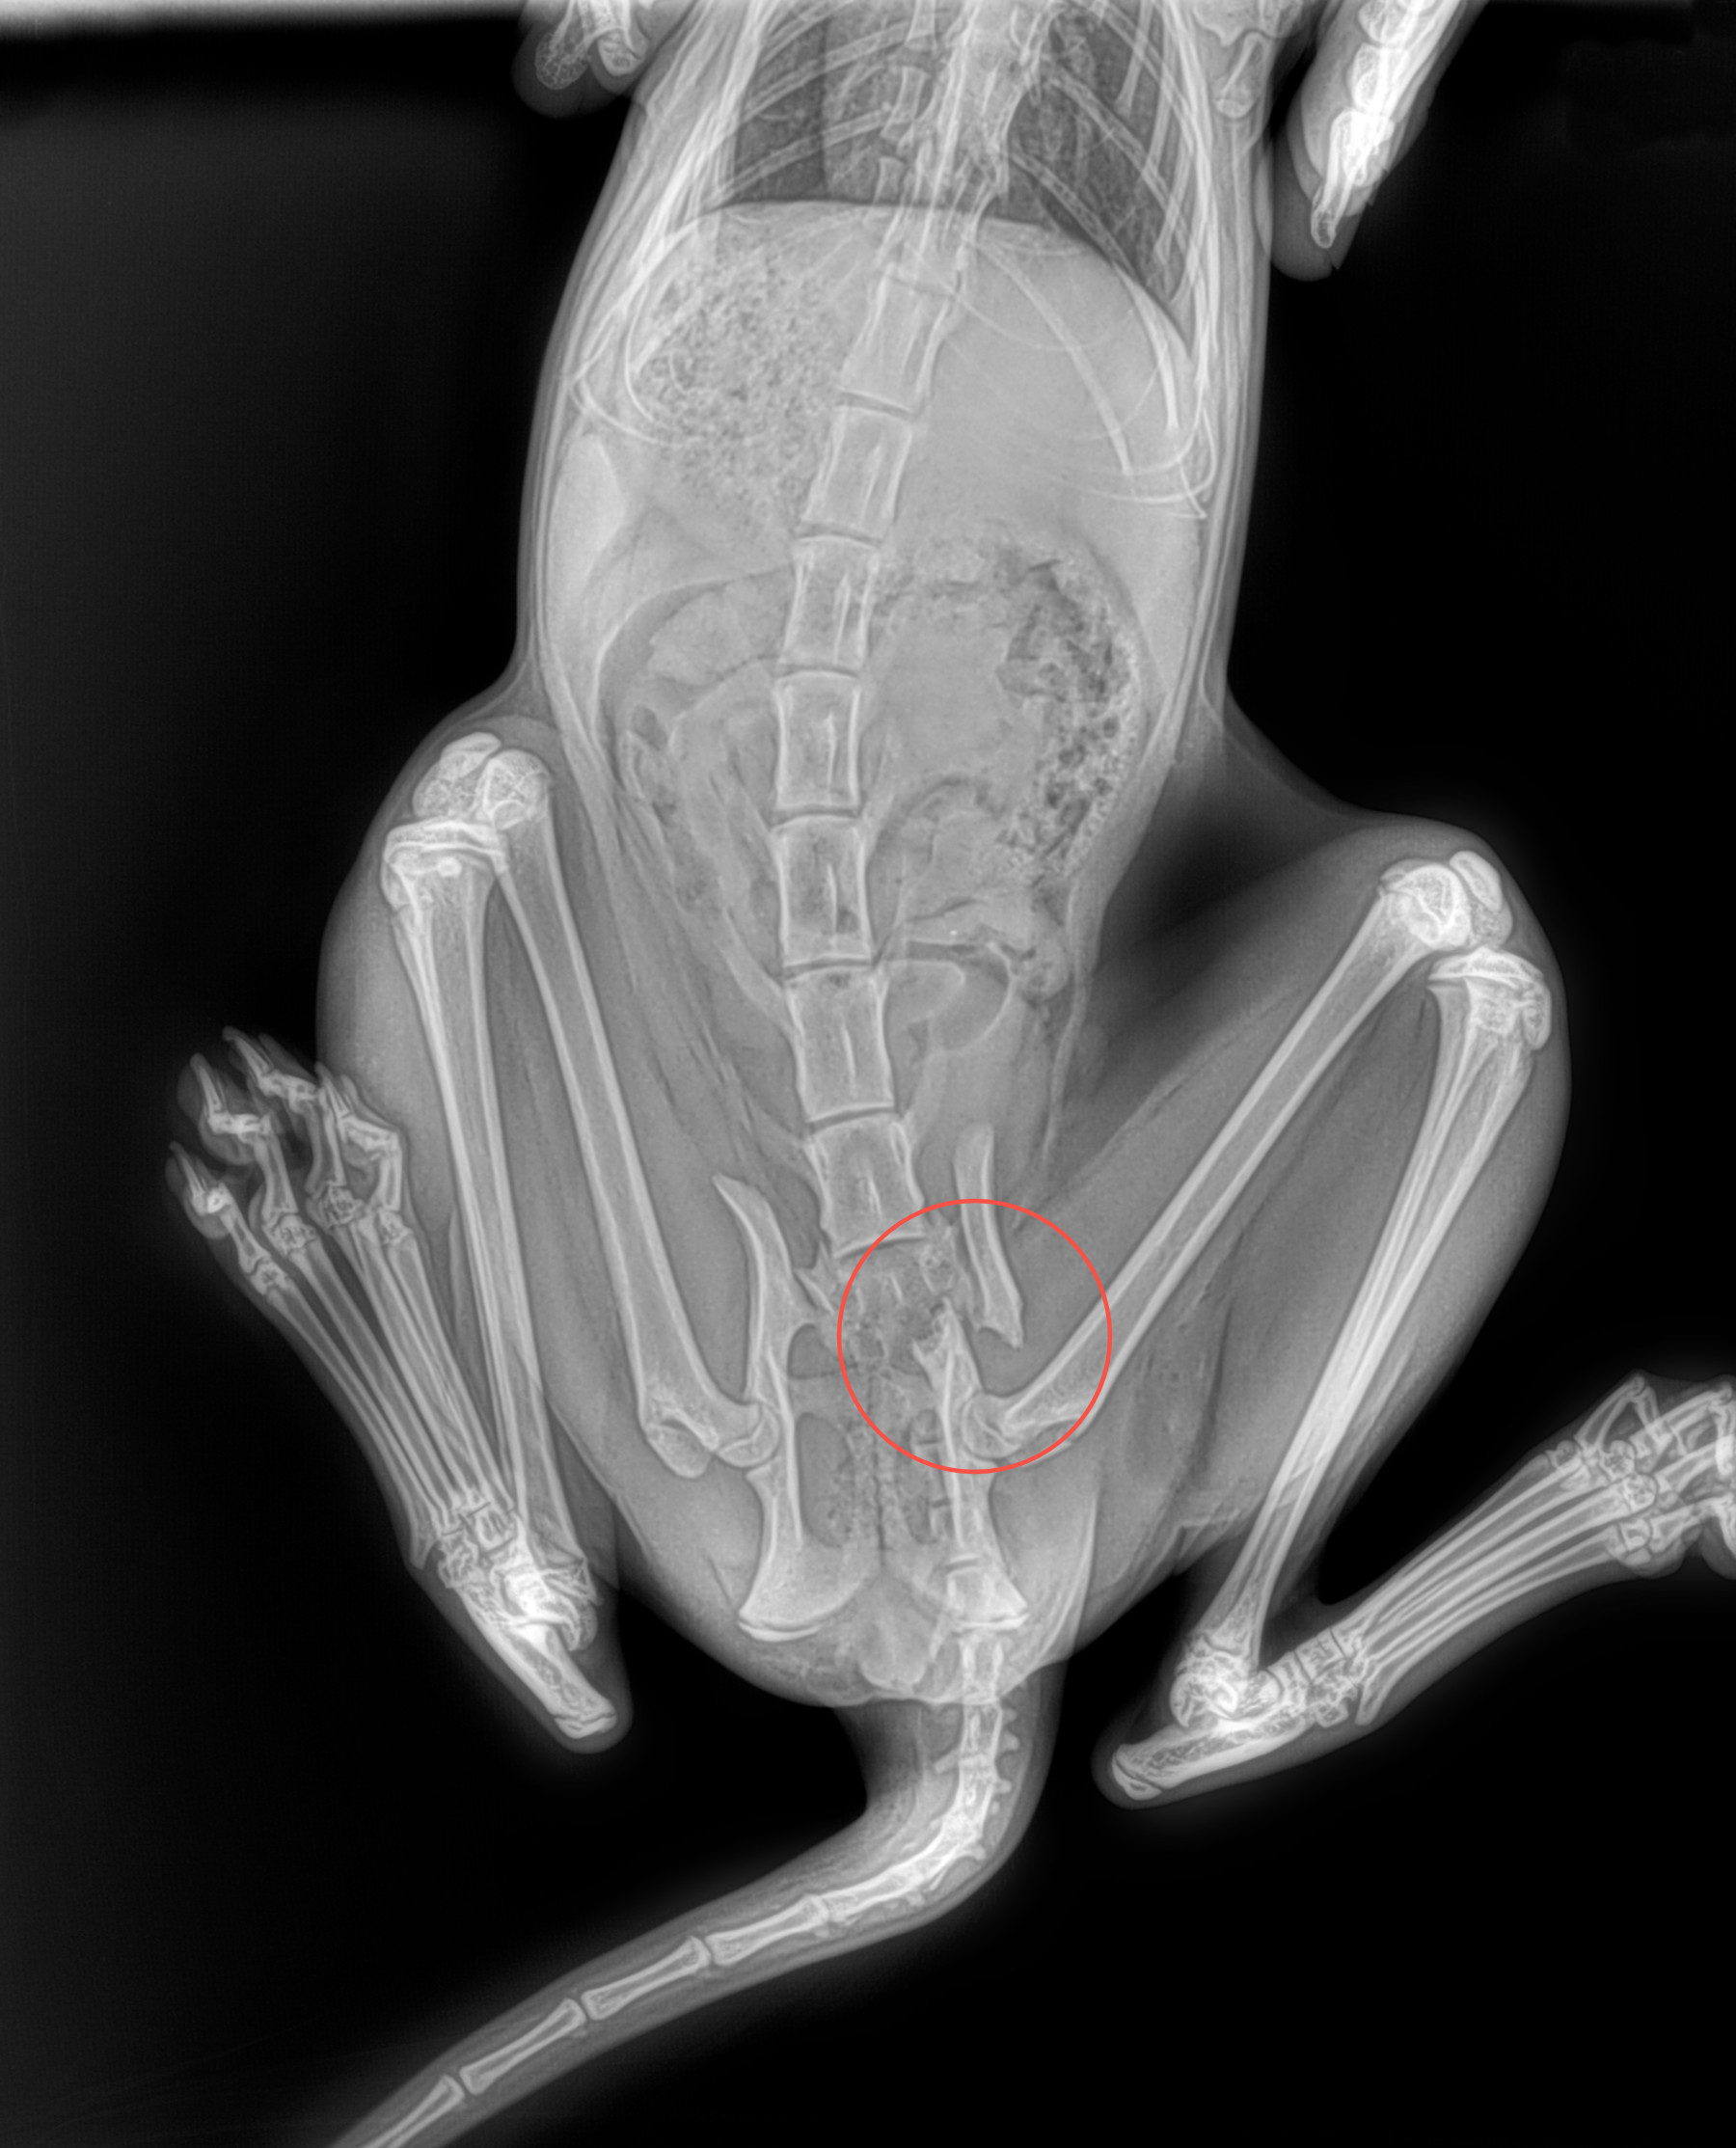

THE GENUS RHYNCHOTERIUM (MAMMALIA-PROBOSCIDEA) in the Hemphilliam - Blancan (NALMA) of central Mexico

In research in Neogene deposits from central Mexico, have collected abundant fossil materials, that have been referred to Rhynchotherium, based in not diagnostic materials and inaccurate age and locality, that not adequately di erentiate between the genus Rhynchotherium, Cuvieronius and Gomphotherium (Lucas y Morgan 2008).